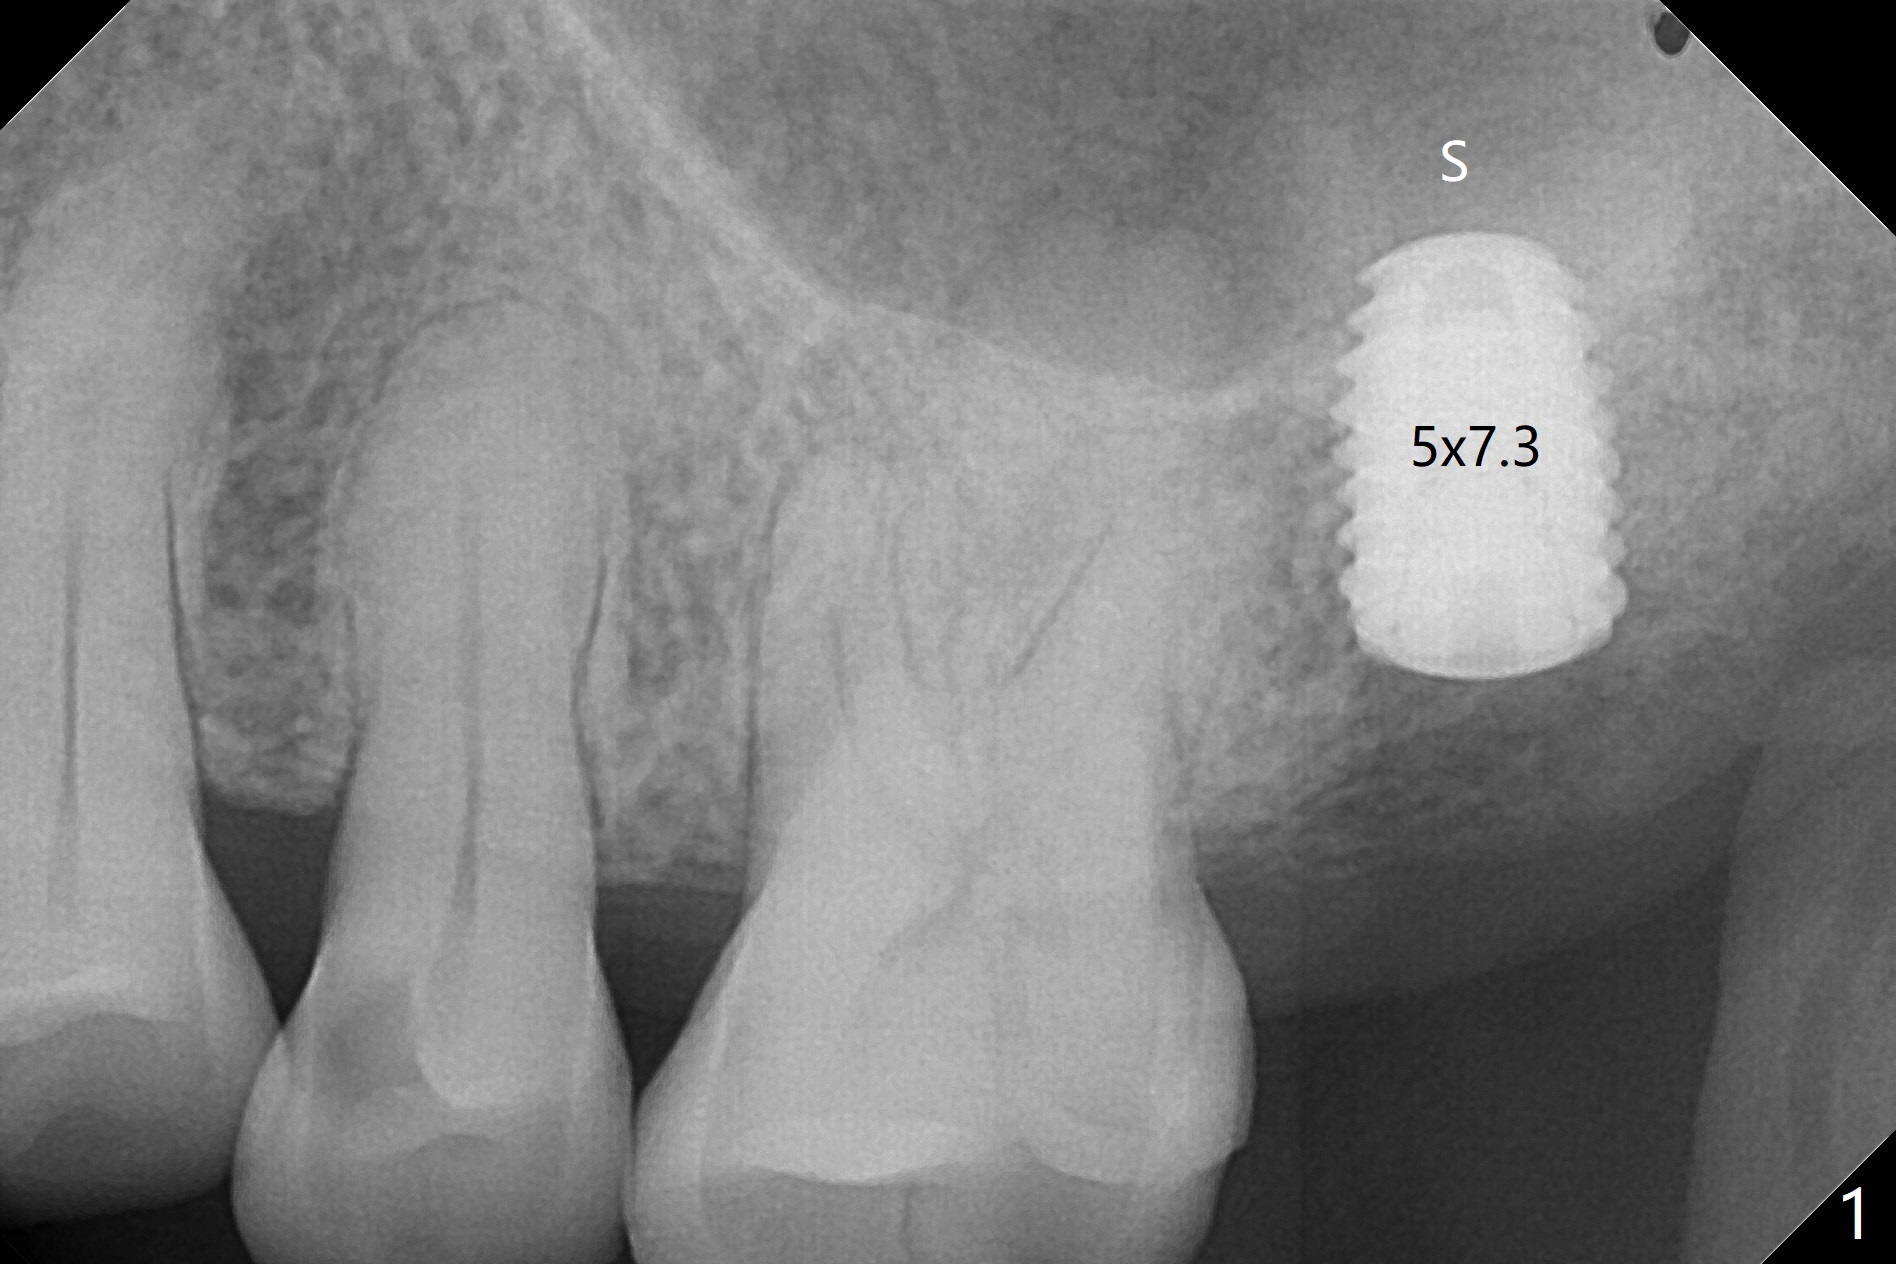

Following shorter drill sequence at #15, sinus round drills (18 and 19 mm long) are used to perforate the sinus floor without membrane tear. With autogenous bone for sinus lift (Fig.1 S), a 5x7.3 mm implant is placed with high torque in spite of using 5 mm cortical drill with 3 O-rings. Clinically there appears no hard tissue distal, although the bone density (graft bone in the 3rd molar socket) is low shown in bitewing (Fig.2 ^). Allograft is applied around the distal coronal portion of the implant before placement of Osteogen Plug and 4-0 PGA suture (Fig.3 *). Profile drill is required during uncover. With sensor I, there is less distortion and angulation (Fig.4, as compared to Fig.1 (sensor II)). A 5.5 mm profile drill is used prior to healing abutment placement.